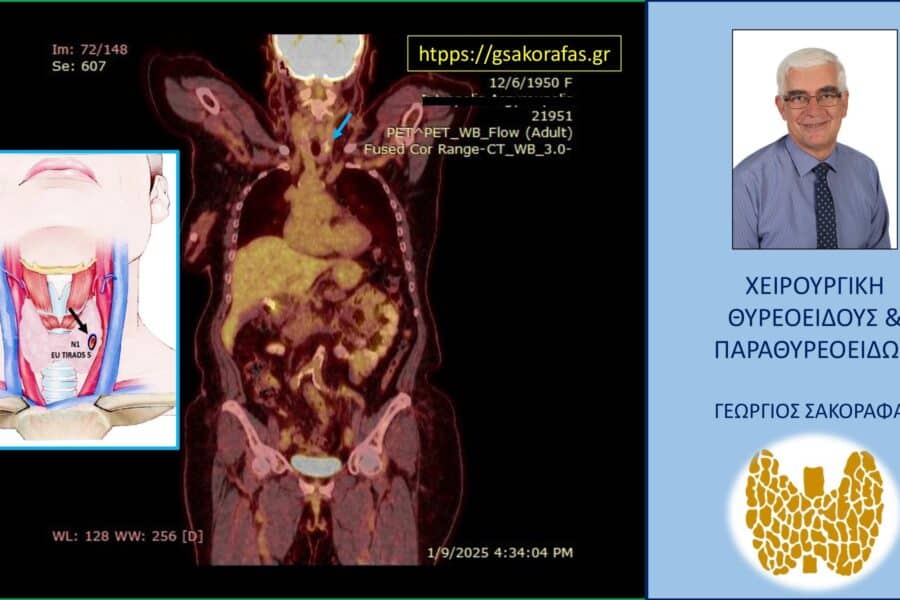

Καρκίνος ΘυρεοειδούςΘηλώδης Καρκίνος Θυρεοειδούς Καρκίνος θυρεοειδούς και μεταστάσεις σε μακρινά όργανα (μακρινές μεταστάσεις) – τι προβλήματα μπορεί να δημιουργήσουν? Καρκίνος θυρεοειδούς και μεταστάσεις σε μακρινά όργανα (μακρινές μεταστάσεις) – τι προβλήματα μπορεί να δημιουργήσουν?…George Sakorafas15 Απριλίου 2026